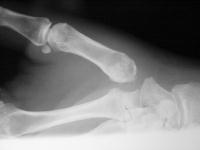

Advanced degenerative changes of the joint: loss of joint space, subchondral sclerosis, large osteophyte, erosions, all with preservation of the adjacent joints.